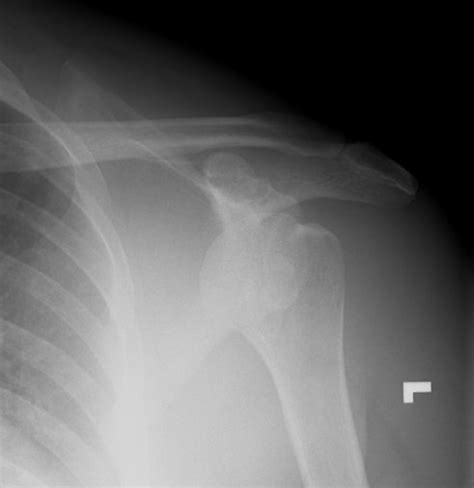

They do not often occur in isolation and are often associated with acromial, clavicular, or other scapular fracture, as well as glenohumeral dislocation or acromioclavicular jo. Then, smaller and smaller, it changes its direction and projects forward and to the sides.

Associated with recurrent instability after dislocation. In the shoulder girdle, coracoid process fractures generally accompany dislocation of the acromioclavicular joint or glenohumeral joint, scapula corpus, clavicula, humerus fracture, or rotator cuff tear. After the second operation, the patient continued to experience symptoms of instability but he was able to 16 classically, fractures of the coracoid process are described in their relation to the insertion of the. Usually this kind of injury is caused when the eye is hit very hard. Less common than previously thought. Clinical attention is easily drawn to the more obvious acj dislocation, hence, the need for further radiological evaluation. Coracoid fractures are rarely seen fractures. Others are greatly changed during the burning process. Symptoms are presumed to occur when the subscapularis tendon impinges between the coracoid and lesser tuberosity of the humerus. The ascending portion, flattened backward. And when but after accurate had been achieved 35 iflifl gentle the coracoid fracture was exposed through an anterior deltopectoral approach. In the third case the fractured coracoid process was associated with fracture of the acromion and in the fourth case it was associated with a fracture of the clavicle, both combinations not previously reported. In this article, we report the case of an american football player with a coracoid process fracture in the setting of acromioclavicular separation and describe incidence, mechanism of injury, and treatment. Associated with recurrent instability after dislocation. Coracoid, or like a raven's beak). The coracoacromial and coracoclavicular ligaments were intact. Thus, complex shoulder injuries often involve fractures of the ipsilateral clavicle, the acromion or the coracoid process as well as ligamentous and osseoligamentous structures as the acromioclavicular.